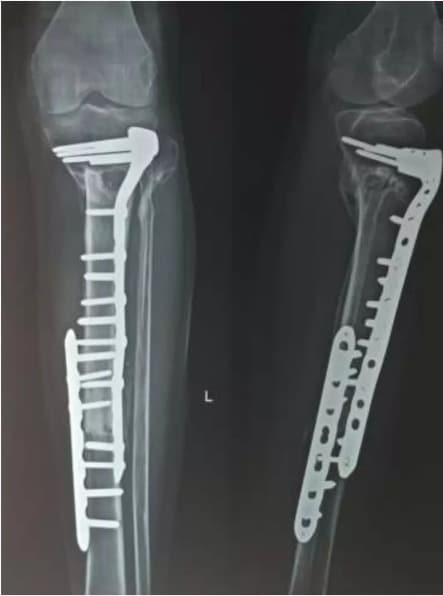

Once the bone is adequately sterilized, it is thawed, prepared, and re-implanted into the patient for biological reconstruction. The treated bone can then be fixed using plates, screws, or intramedullary devices.